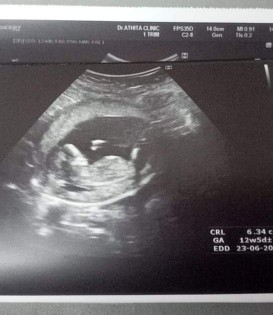

12วีคคะซาวมาเมื่อวาน

12w น้องเปนตัวแล้วค่ะ

12สัปดาห์แล้วค่ะ